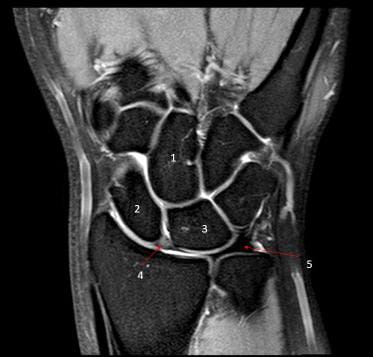

9. Observe a imagem acima do corte axial do punho. Qual a estrutura rotulada com o número 1?